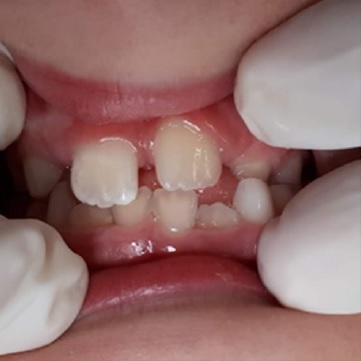

On intraoral examination at the dental office, tooth 21 was missing, and the marginal gingiva was lacerated. On inspection and palpation of the anterior maxillary segment, dentoalveolar fracture was ruled out. The patient had no relevant medical history.

The patient’s parents were informed about a possible poor outcome of the replantation of the avulsed tooth (e.g., root resorption, ankylosis, tooth discoloration, or tooth loss), which had endured an extraoral time of approximately seven hours. Even so, the parents decided to replant the tooth and signed an informed consent.

The avulsed tooth had an intact crown and a two-thirds formed root with a wide-opened apex. The dentist seized the tooth from the saline solution, holding it by the crown and not touching the root surface, and gently rinsed it with 0.12% chlorhexidine. Local anesthesia (2% lidocaine hydrochloride with 1:100000 epinephrine vasoconstrictor) was administered through labial and palatal infiltration in the affected area. The alveolar socket was gently rinsed with saline solution. The avulsed tooth was restored into the socket with slight digital pressure, ensuring its correct position. The replanted tooth was splinted with a 0.4-mm stainless steel orthodontic wire and brackets, placed on the left deciduous canine (63), the right maxillary central incisor (11), and the right deciduous canine (53) (Figure 2). The brackets were fixed away from the gingival tissues and proximal areas after etching the crown surfasse with 37% phosphoric acid for 20 seconds, rinsing with water, air drying, and applying a bonding agent and a composite resin.